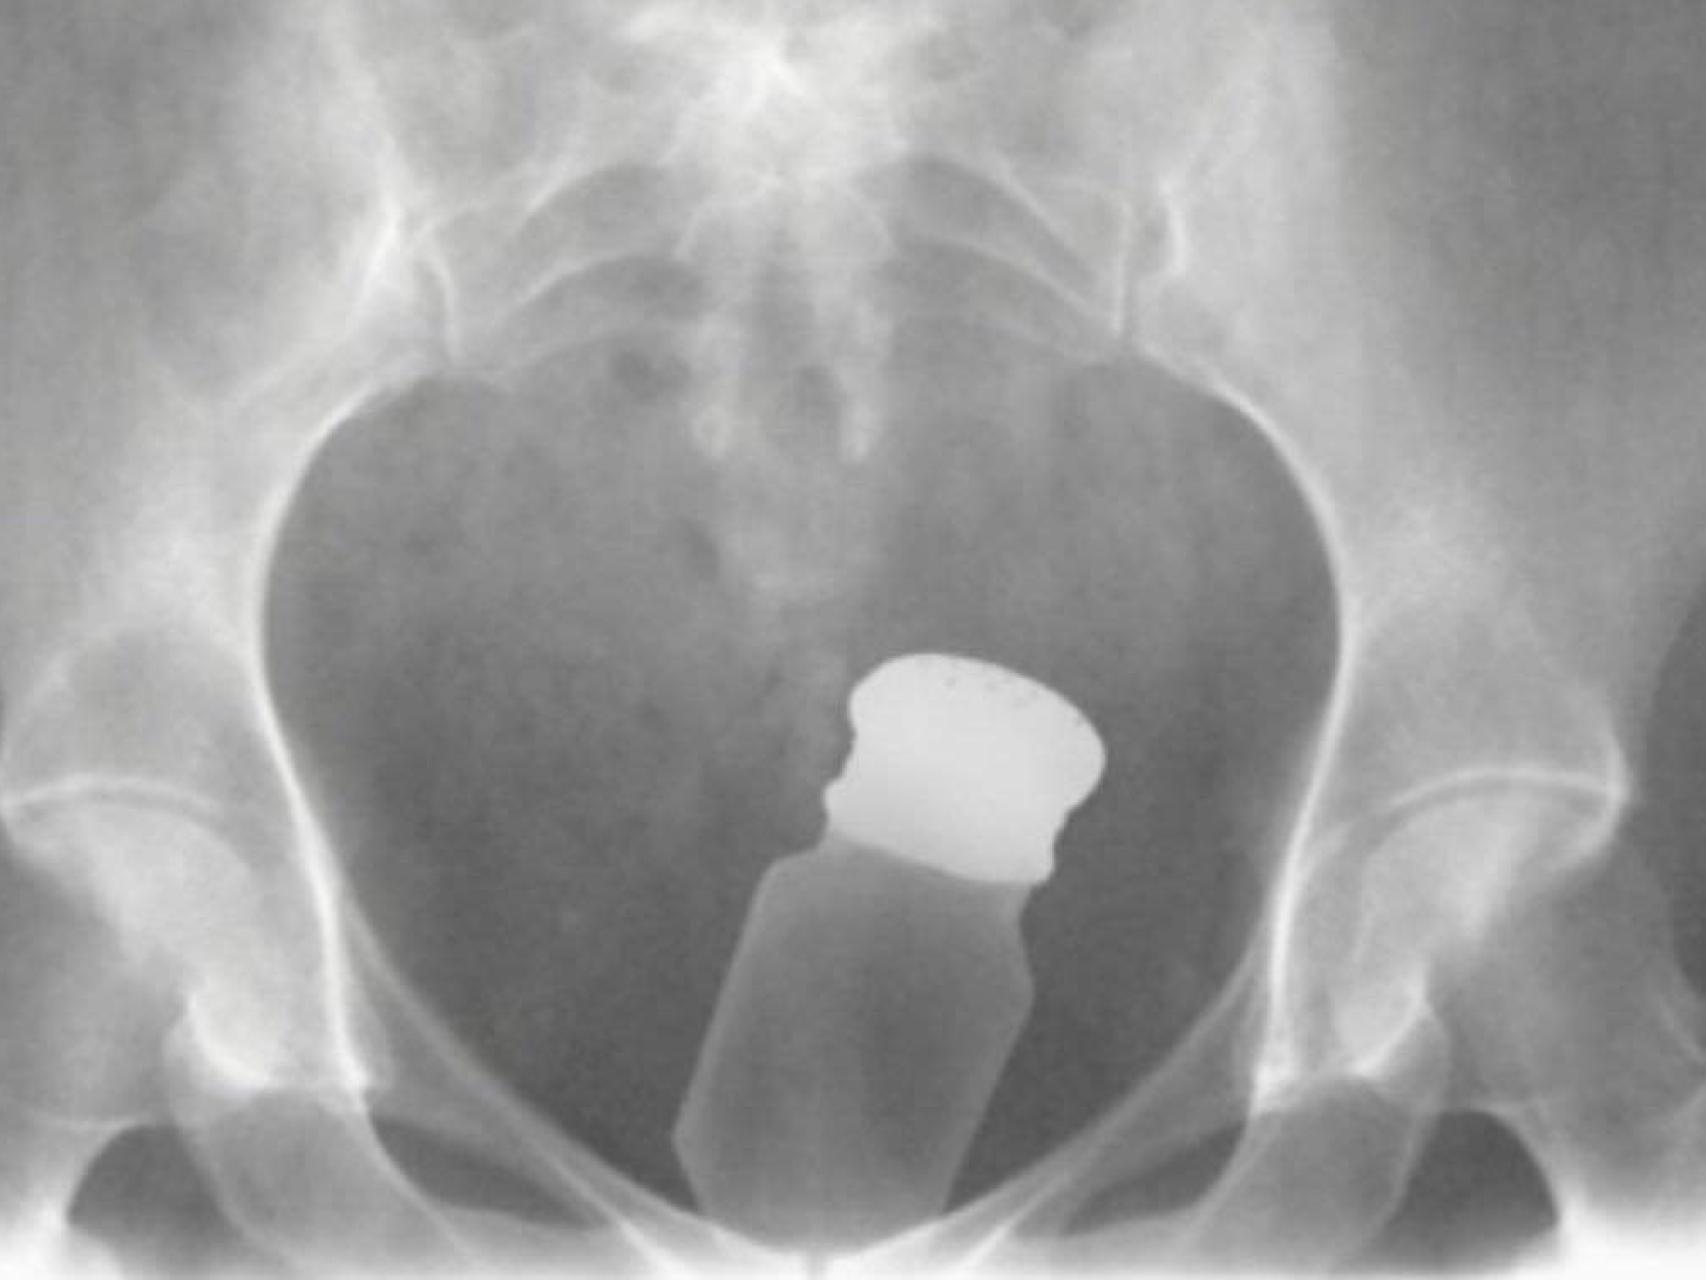

Una radiografía que muestra cómo se introduce la droga en los penales: dentro del cuerpo